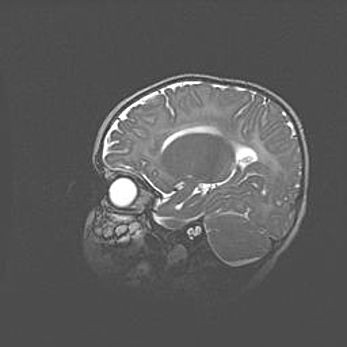

Сообщающаяся гидроцефалия. Кистозная энцефаломаляция головного мозга.

Возраст: 3 месяца 4 дня

Вес: 3100 г

Пол: женский

Окружность головы: 34 см

Срок гестации: 31 неделя

Кистозная энцефаломаляция головного мозга - одна из форм поражения головного мозга в детском возрасте. Характеризуется возникновением множественных и распространённых кист в коре, белом веществе и подкорковых образованиях головного мозга у плодов, новорождённых и детей раннего возраста. Развитие кистозной энцефаломаляции связано с внутриутробной асфиксией и гипотонией, родовой травмой, тромбозом синусов, пороками развития сосудов, инфекциями, сепсисом и другими причинами. Наиболее значимые инфекционные агенты: вирусы простого герпеса, цитомегалии, краснухи, токсоплазмы, энтеробактерии, золотистый стафилококк и другие.